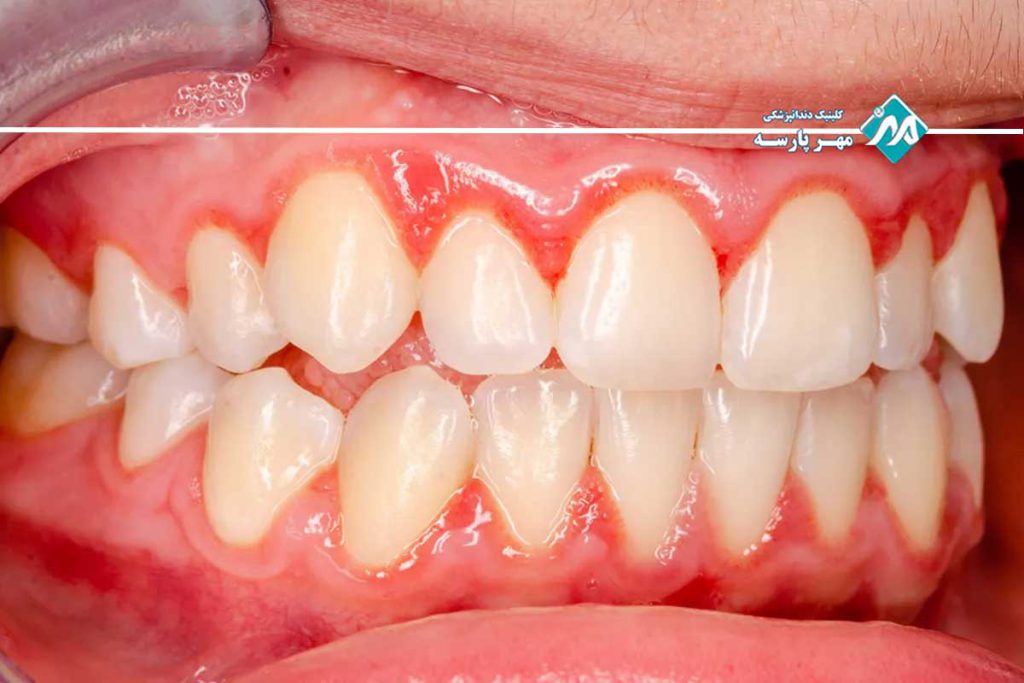

پریودنتیت یک مرحله پیشرفتهتر از ژنژیویت است که زمانی رخ میدهد که التهاب به لایههای عمیقتر لثه نفوذ کرده و به بافتهای حمایتی دندانها آسیب میزند. در این نوع بیماری لثه، لثهها از دندانها جدا شده و فاصلههایی به نام پاکتهای پریودنتال ایجاد میشود که محل مناسبی برای رشد باکتریها هستند. علائم پریودنتیت شامل خونریزی مداوم لثهها، بدبویی دهان، احساس درد در هنگام جویدن و دندانهای شل شده است. در صورتی که پریودنتیت درمان نشود ممکن است باعث تخریب دائمی استخوان و بافتهای اطراف دندانها شود و حتی منجر به از دست دادن دندانها گردد. درمان این بیماری معمولاً شامل پاکسازی عمقی دندانها و در برخی موارد جراحی لثه است.

- دندانهای شل یا جابجا شده: در مراحل پیشرفتهتر بیماریهای لثه، لثهها ممکن است از دندانها جدا شوند و باعث شل شدن یا جابجایی دندانها شوند. این وضعیت در پریودنتیت و پریودنتیت پیشرفته دیده میشود.

- تغییر در ظاهر لثهها: لثهها ممکن است از دندانها فاصله بگیرند و شکافهایی به نام پاکتهای پریودنتال ایجاد شود که محل تجمع باکتریها و عفونت است.